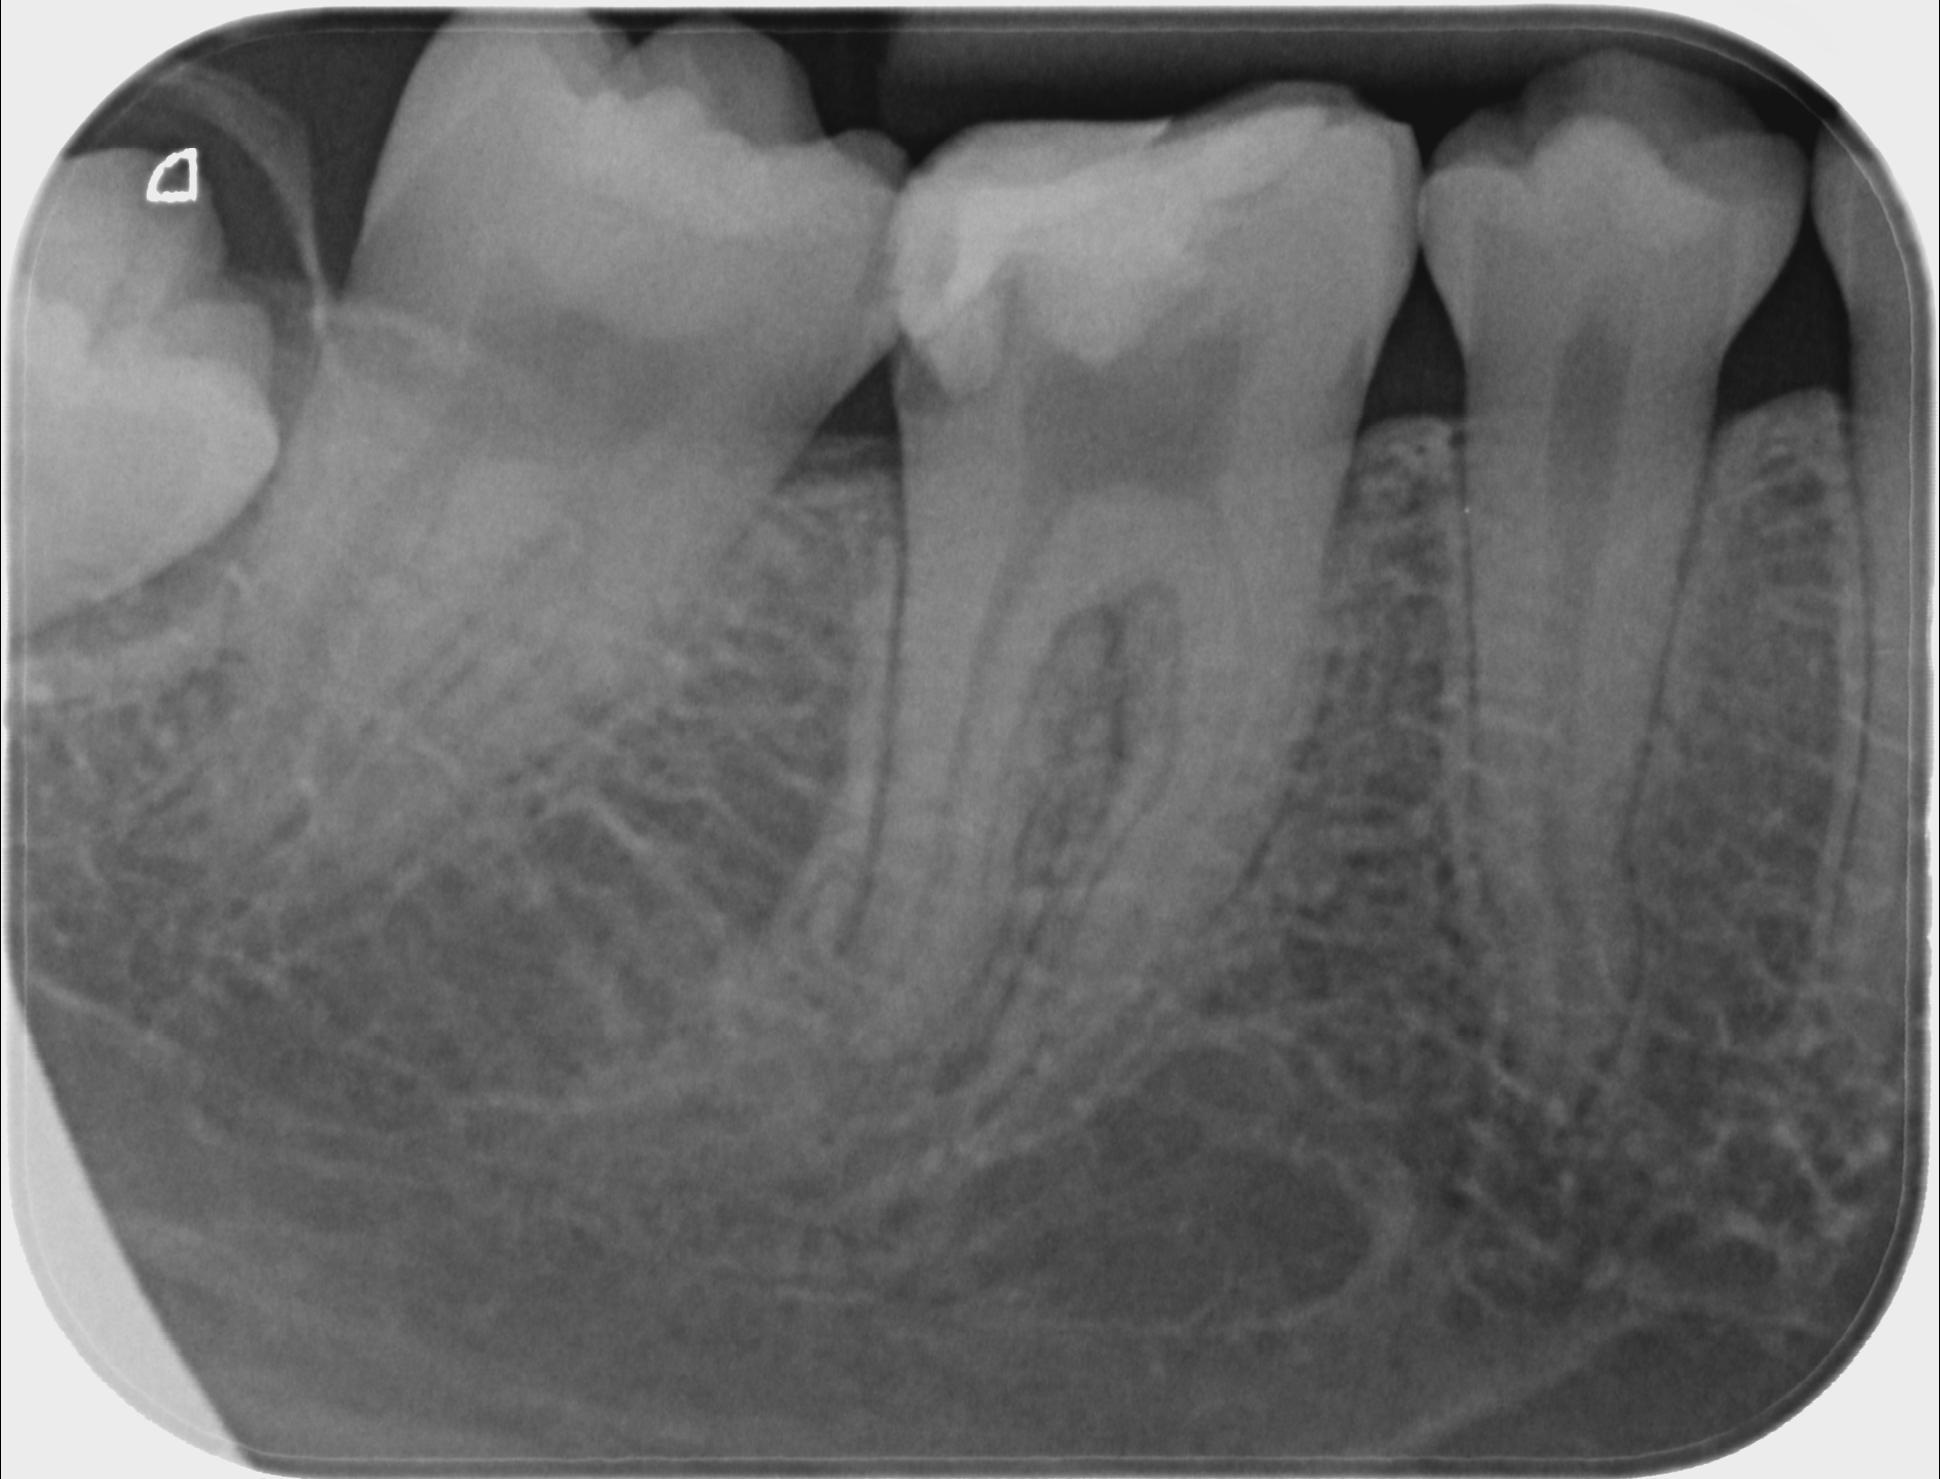

Ein Beispiel für eine Einzelzahnaufnahme, bei klinisch und optisch nicht erkennbarer Karies an Zahn 46 und als Nebenbefund ein verlagerter Weisheitszahn 48 distal.